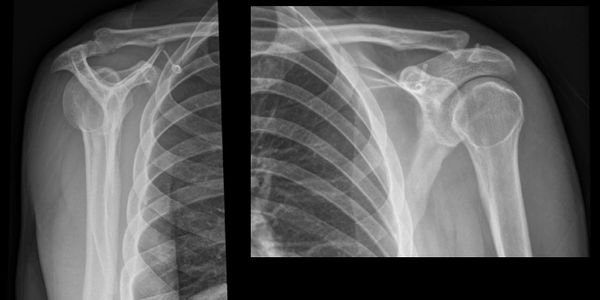

Reverse Hill-Sachs lesion seen here (left) on an Xray from a patient who had sustained a posterior dislocation following a seizure. Also called a McLaughlin lesion, this is an impact fracture of the postero-medial humeral head.

The humeral head sits posterior to the glenoid rim, twisting slightly into internal rotation with a resultant “lightbulb” sign seen on X-Ray in the AP view. A “reverse Hills-Sachs”/McLaughlin lesion may also be seen, this is an impact fracture of the anteromedial humeral head. The posterior dislocation can be missed on X-ray, so think about it if you have a patient reluctant to externally rotate their humerus, especially if confused or post-ictal. CT scan if X-Ray unclear or if you can’t get a decent axial view.